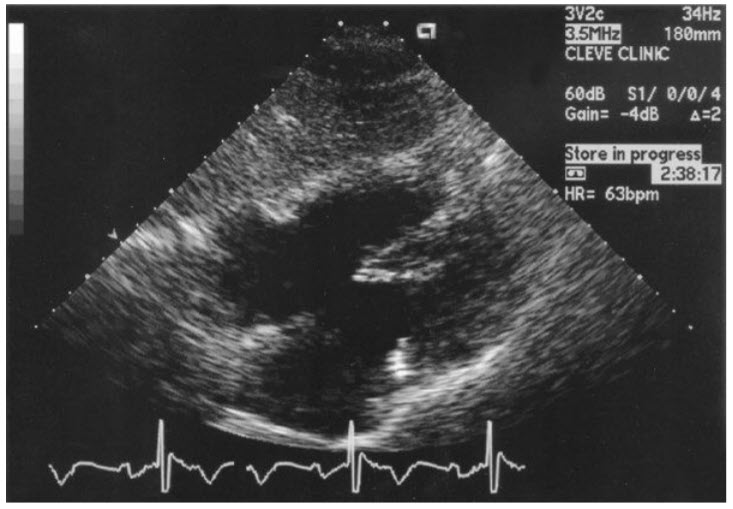

Subcostal four-chamber view. ASDs and anomalous pulmonary venous return should be suspected in patients with unexplained RV dilatation and volume/pressure overload (figure below).

The findings of RA and RV dilatation in the apical four-chamber (A4C) view (A) and significant right-to-left shunting of agitated saline (B) are highly suggestive of an ASD ± anomalous pulmonary venous return. A secundum ASD is confirmed as a defect in the midportion of the interatrial septum, best seen in subcostal scan plane (C) and with color flow Doppler (D). ASD, atrial septal defect; RA, right atrium; RV, right ventricle.

A secundum ASD is the common type of ASD and is located centrally in the interatrial septum at the site of the fossa ovalis. The defect may be single, multiple, or fenestrated. This defect is best viewed by transthoracic echocardiography in the subcostal view (due to ultrasound waves being better reflected off the interatrial septum in this view). Coexisting partial anomalous pulmonary venous drainage is seen in 5% of patients with a secundum ASD. The atrial septal defect occurs when the interatrial septum is deficient at the crux of the heart/level of the atrioventricular valves. A primum ASD occurs as part of the spectrum of AVSD. Partial AVSD commonly describes a primum ASD in combination with a so-called cleft mitral valve, more correctly described as a trileaflet left-sided AV valve. Primum ASDs are often well demonstrated from the apical four-chamber view (± subcostal) in association with mitral regurgitation from a trileaflet left-sided AV valve (figure below).